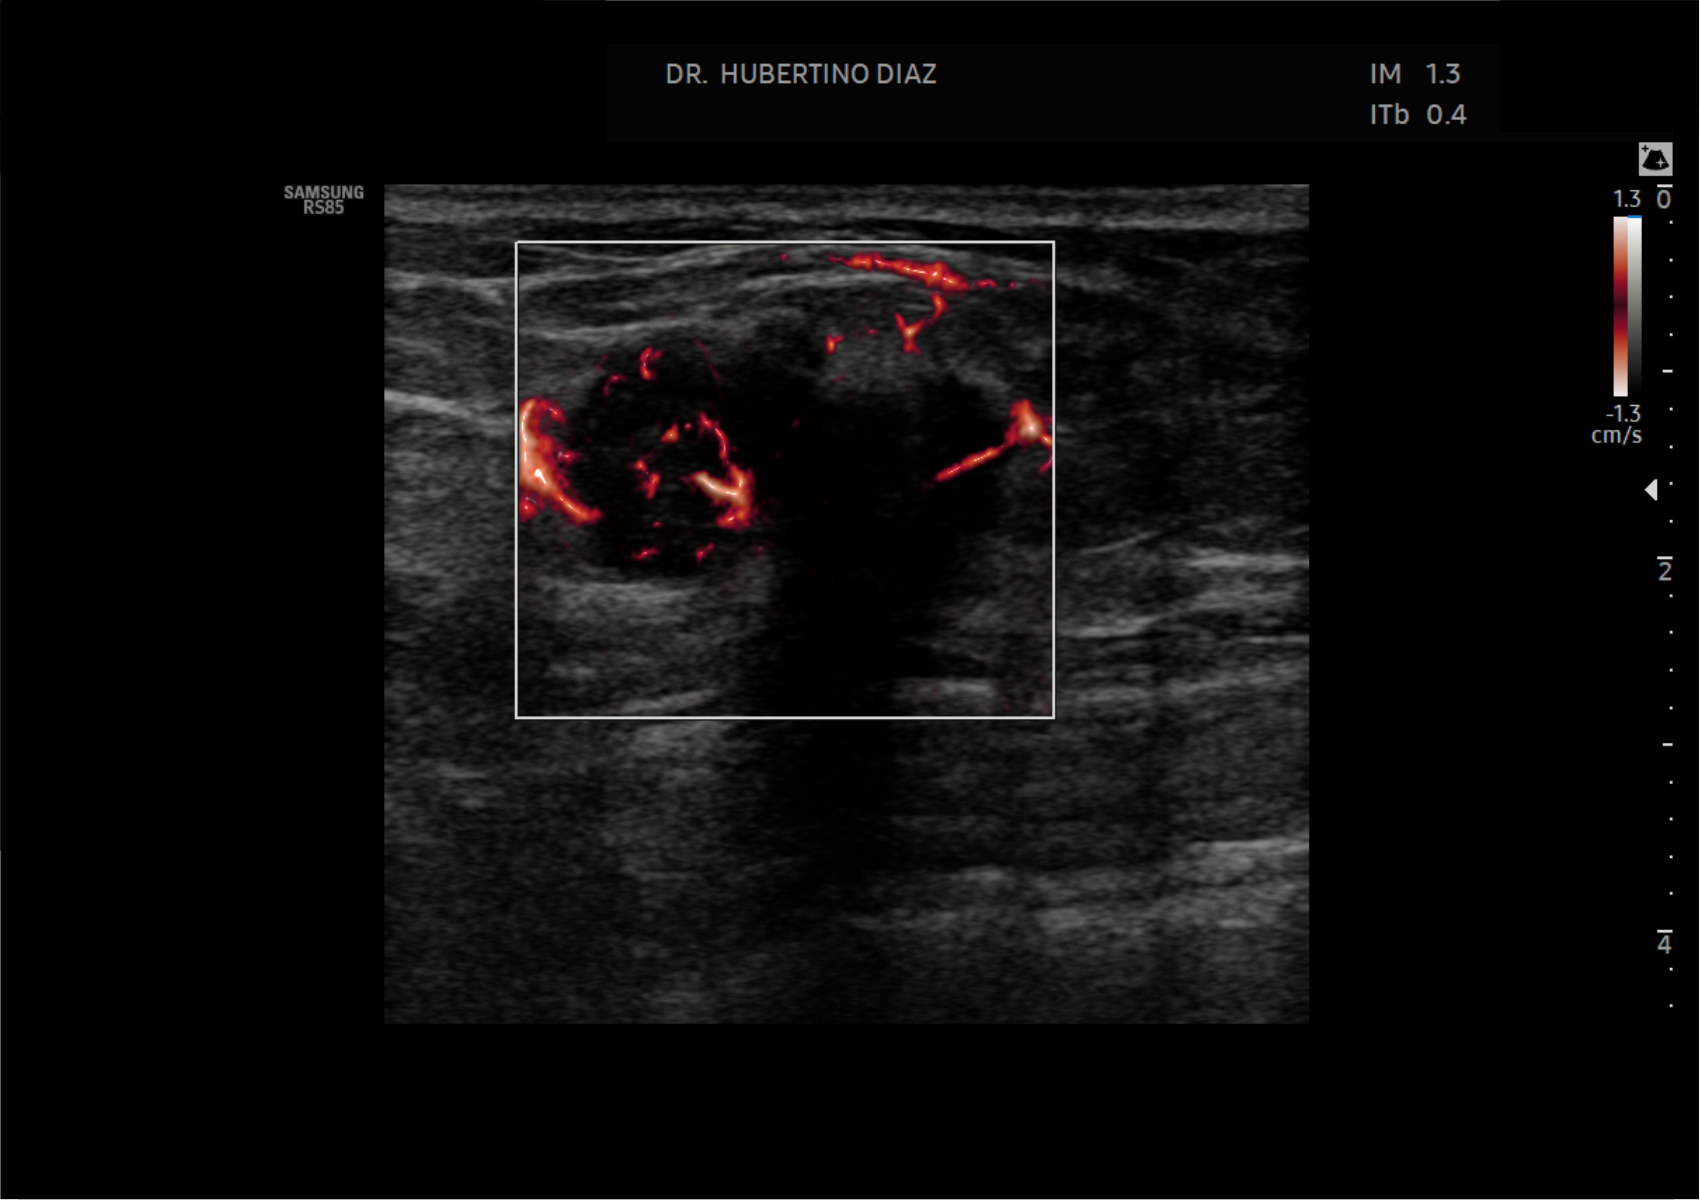

La ecografía Doppler de microflujo de mama es una tecnología avanzada de ultrasonido que permite evaluar la microvascularización de los tejidos mamarios con mayor sensibilidad que el Doppler convencional. Este método, también conocido como Doppler de tercera generación, permite detectar vasos sanguíneos muy pequeños y flujos de baja velocidad, lo que mejora la caracterización de lesiones mamarias.

Mediante ultrasonido de alta resolución y Doppler de microflujo, este estudio permite analizar la vascularización de nódulos y lesiones mamarias, información clave para diferenciar entre lesiones benignas y sospechosas, así como para complementar la evaluación ecográfica de la mama.

La ecografía Doppler de microflujo de mama en Lima es especialmente útil en la evaluación de nódulos mamarios, tumores de mama, procesos inflamatorios y seguimiento de lesiones detectadas en ecografía o mamografía, aportando información adicional sobre el patrón vascular de las lesiones.